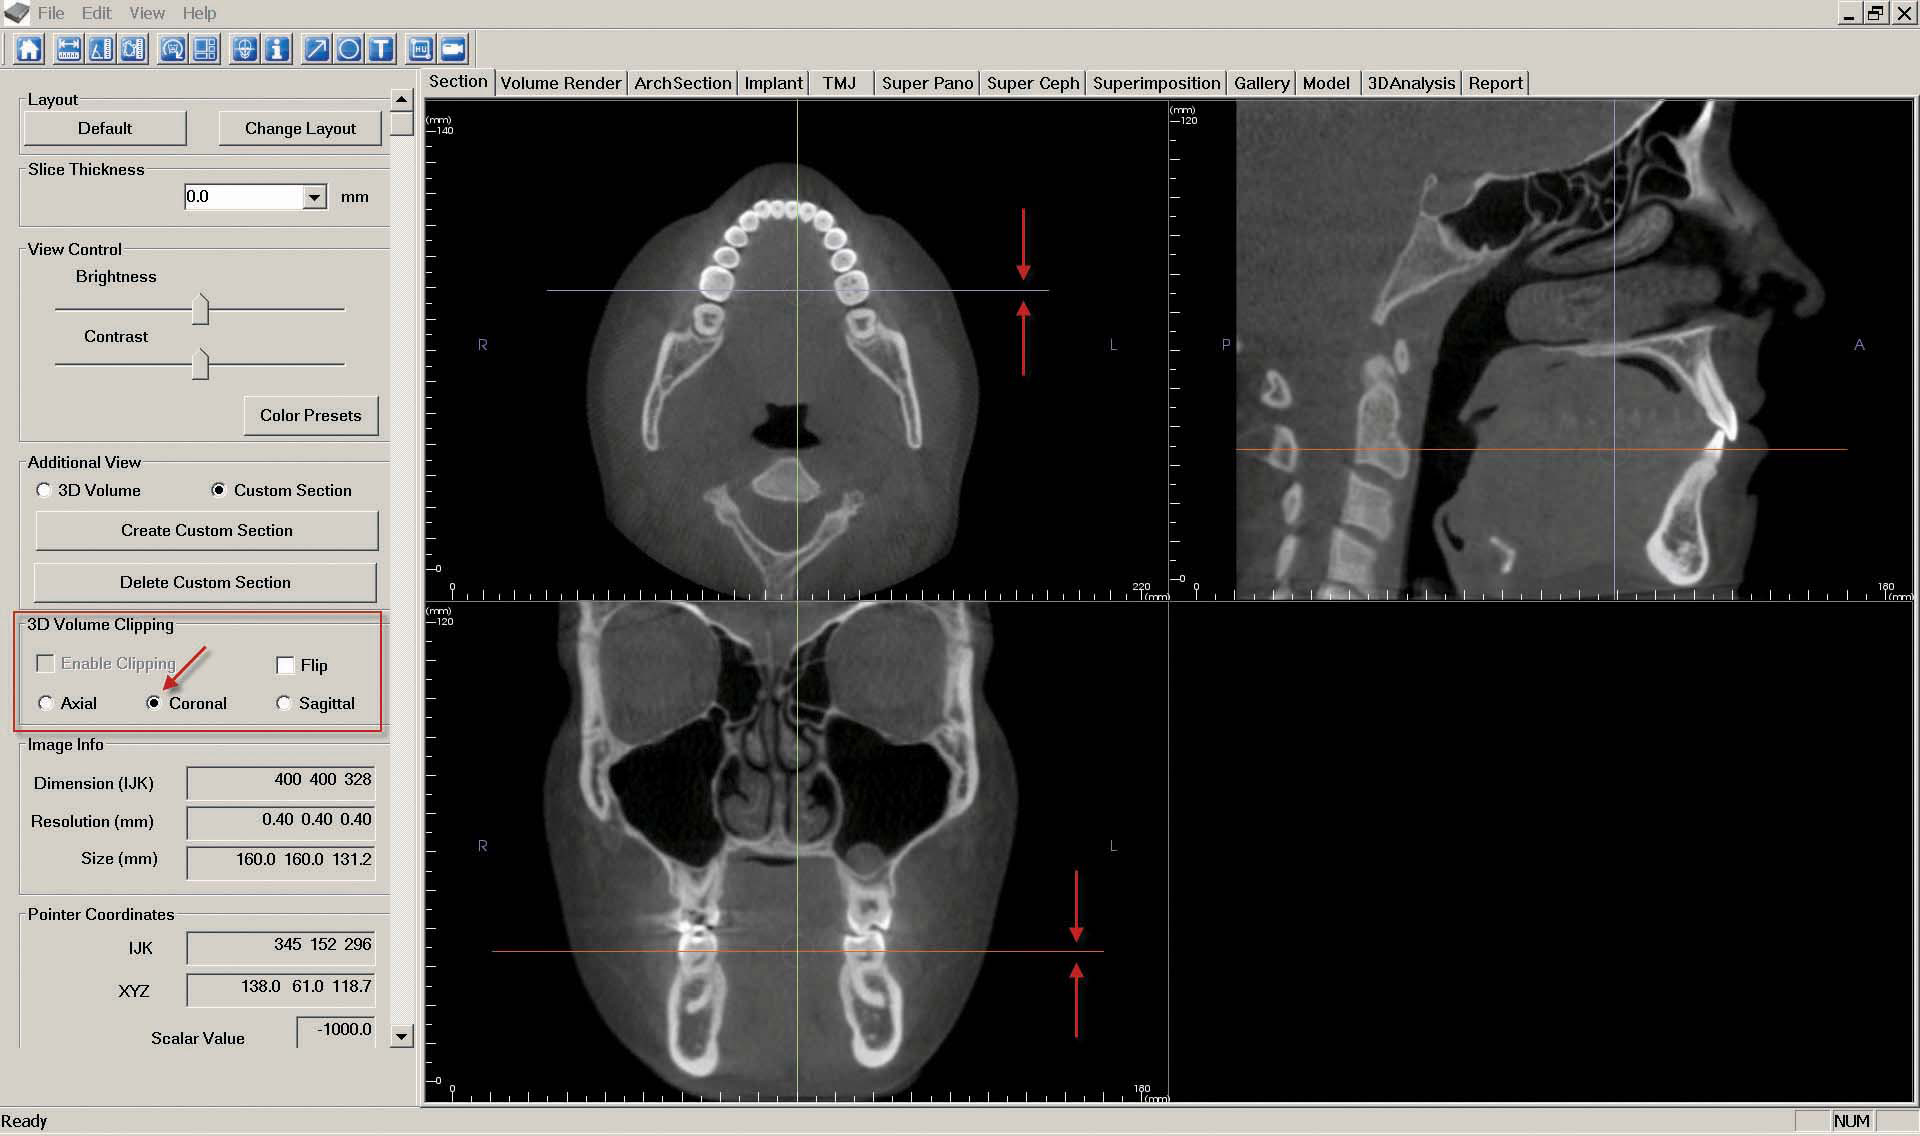

c. The "Coronal Slice" is created by navigating to the "Section" tab. First, ensure the patient is correctly oriented. To adjust the orientation, click the "Reorientation" icon at the top of the screen.

Once the orientation is correct, adjust the orange line in the bottom left image until the top left image shows a clear view of the lower arch. Next adjust the purple line in the upper left image while looking at the image below until there is a clear coronal slice of the first molars.

In the "3D Volume Clipping" section on the left-hand side of the screen, select "Coronal."

If desired, click the "Toggle Cursor Visibility" icon to remove reference lines. As described in step 7, "Capture to Gallery" and select "Coronal" in the "Select Image to Capture" pop-up window. Click "OK," then name the image "Coronal Slice."